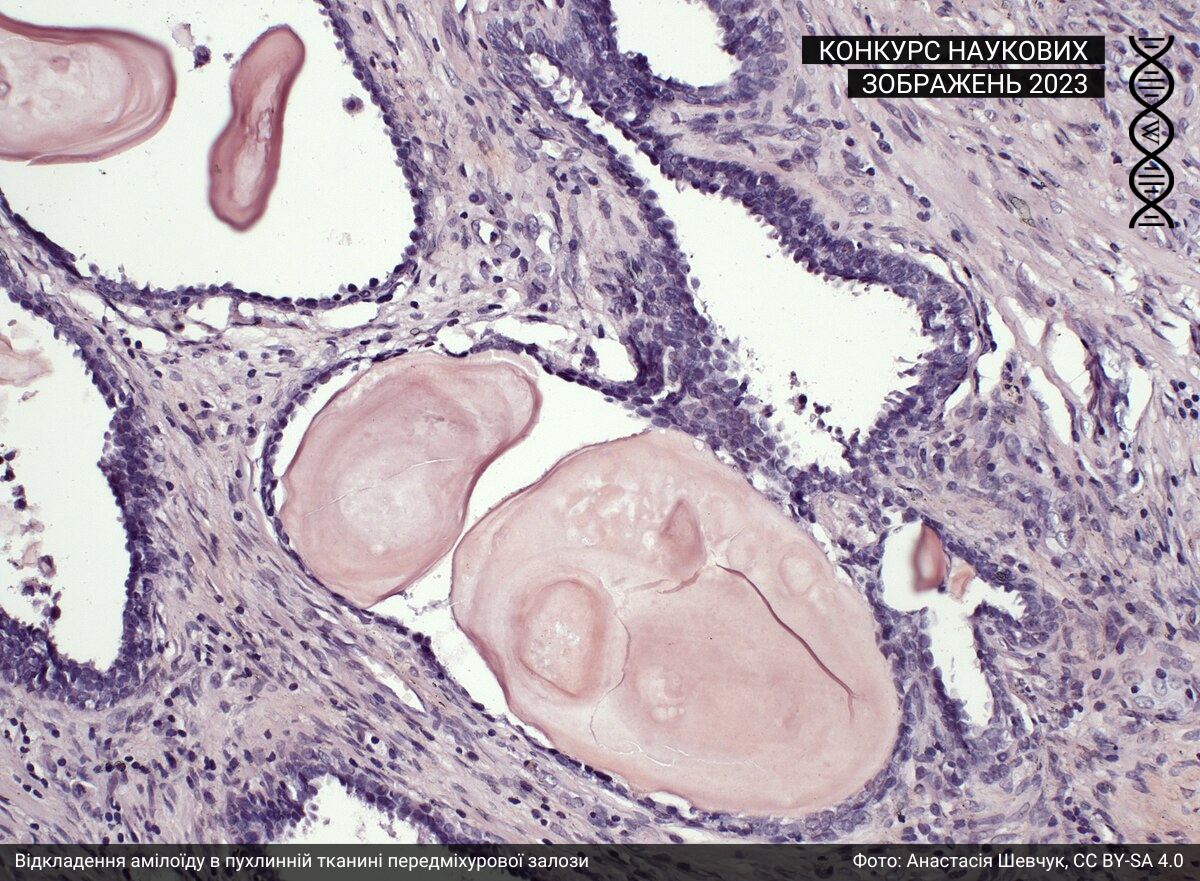

Мікроскопія

Під цю категорію підпадають світлини, зроблені за допомогою різних методик мікроскопії. Минулого року до цієї категорії учасники та учасниці завантажили 43 фотографії.

Спеціальна відзнака журі

Журі призначили спеціальну відзнаку серії зображень однієї авторки: https://w.wiki/99qJ, https://w.wiki/99qK, https://w.wiki/99qL, https://w.wiki/99qM